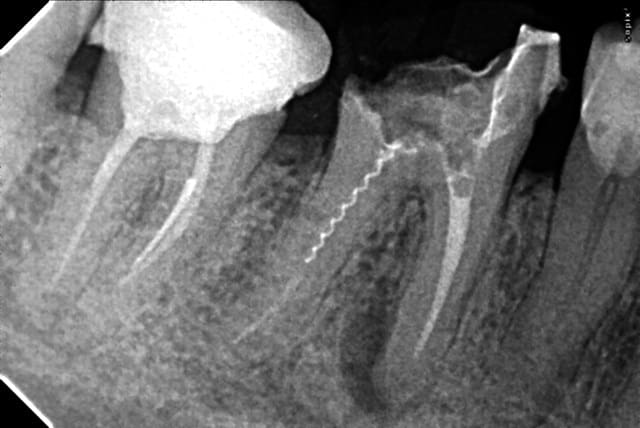

Je reviens sur ce cas à l'image curieuse. patient venu en urgence et je m'étais démerdé pour faire le TT en un RDV quitte à modifier quelque peu mon planning de la journée ( léger retard).

Et là, un gros canal latéral ou un coup de pro-taper retraitement mal placé ??